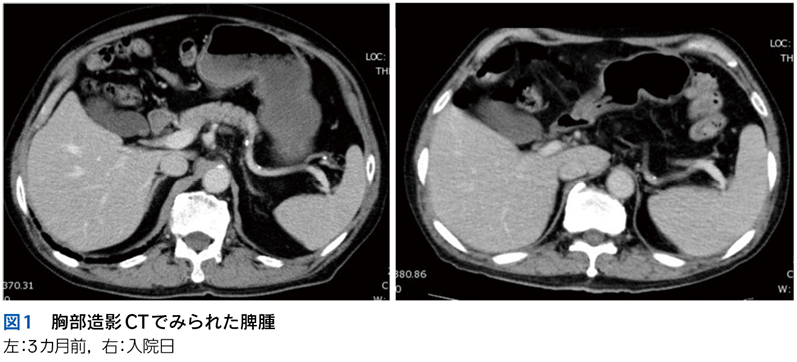

▶ こちらは初期評価不十分のまま多数の介入がなされたケースである。患者が呈している「プロブレム」をまとめて,「皮疹,肝機能異常,腎障害,汎血球減少を伴う遷延性発熱」とフレーミングし,たとえば血管内リンパ腫や血球貪食を伴う成人スティル病などを考えることも可能だが,現在の症状や検査異常(の一部)は抗菌薬をはじめとした介入の副作用として生じているのかもしれない。すべてのプロブレムが一元論で説明されない可能性も考慮したフレーミングも用意するのが謙虚な態度だろう。